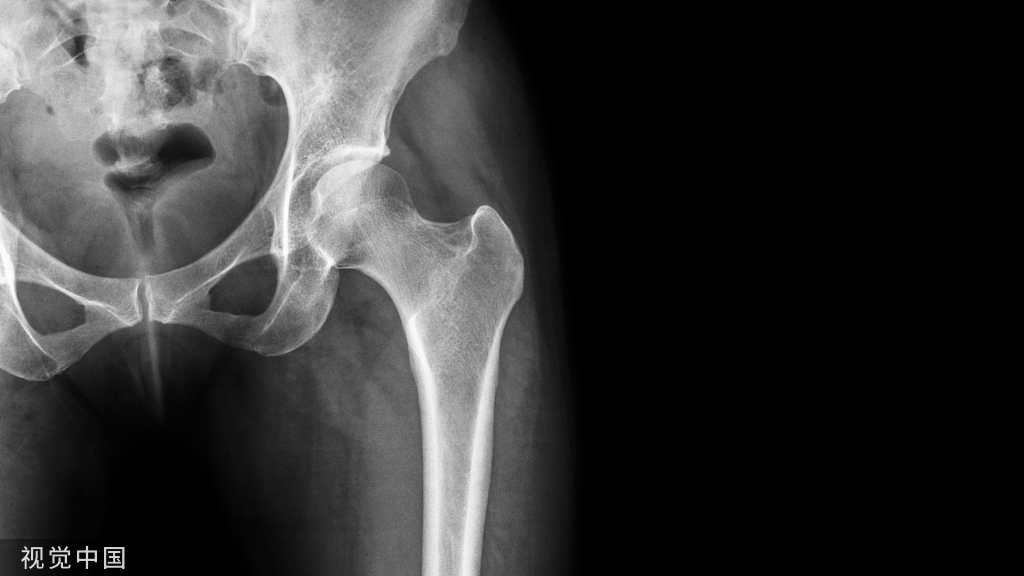

图2  84岁患者,III型骨折,伴有内侧壁骨块,未复位,术后1月复查良好(c),术后3月复查螺钉切出(d)。